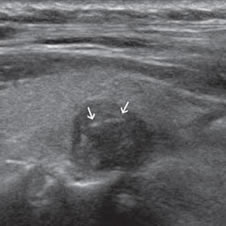

Figura 9. Cáncer papilar, de forma redondeada, de 30 mm de diámetro,

hipoecogénico, con microcalcificaciones periféricas y discontinuas

(flechas). En el aspecto posterior las microcalcificaciones

forman un contorno lineal (flecha abierta).